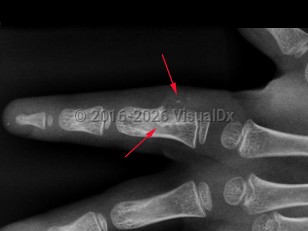

Periosteal chondroma in Adult

A rare, benign cartilage tumor that typically occurs in the long tubular bones, but also commonly develops in the proximal humerus and short tubular bones of the hands. Periosteal chondroma develops on the surface of the bone, the periosteum, a membrane covering the bone. The tumor may develop in children and adults.

The precise cause is unknown. Patients with periosteal chondroma are typically asymptomatic. In some patients, symptoms include pain, swelling, palpable mass, or broken bone. Pain as a symptom may be an indication of a malignant tumor. In most cases, periosteal chondromas do not spread to other body parts, but they may continue to grow; some may become cancerous in adulthood.